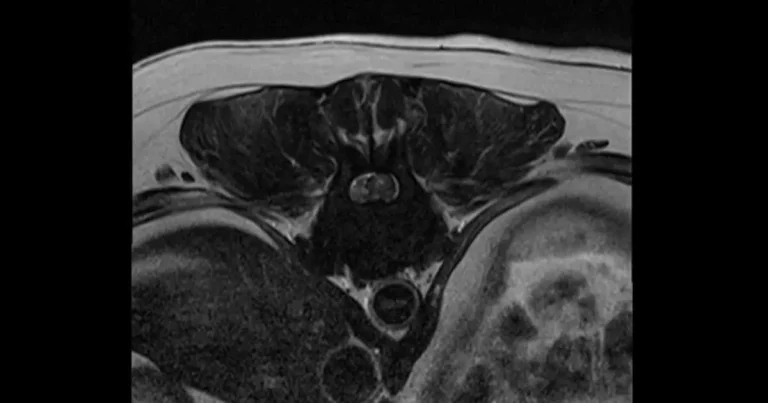

Figure 1. Transverse view of thoracolumbar intervertebral disc extrusion (type I; disc material can be seen as a crescent shaped compression on the left).

The most common spinal condition (Holzman, 2023) is intervertebral disc disease (IVDD) – the herniation of the disc material that causes compression of the spinal cord leading to pain, weakness and paralysis (Dorn, 2022). It is the most common spinal condition.

Different disc herniation types can be classified into two subsections (Carver, 2016, Fenn 2020), as seen in Table 1.